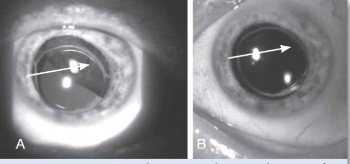

בבדיקה של החולה תתגלה מסה, לרוב מלנוטית, בענביה, שיכולה להיות ממוקמת אנטומית בחלק הקדמי של העין (בקשתית) או בחלקים האחוריים של העין (בגוף הריסני או בשכבה הדמית) (תמונה 1, תמונה 2). גידולים גדולים יכולים לערב שני אזורים אנטומיים, ולעתים אף את כל השלושה. אישוש האבחנה נעשה באמצעות בדיקת על-קול של העין הנגועה. אחוז הטעות בדיוק באבחנה של מלנומה של הענביה הוא רק 0.3% על פי ה-Collaborative Ocular Melanoma Study (COMS Study)[1].

למיקום האנטומי של הגידול יש משמעות פרוגנוסטית. מלנומה של הקשתית מהווה כ-5% מכלל המלנומות של הענביה, וגידול זה נחשב לפחות תוקפני מבחינה ביולוגית. במעקב ארוך טווח נמצא שמלנומה של הקשתית נוטה לשלוח גרורות רק ב-3% מהמקרים, ב-5% וב-10% במעקב של חמש שנים, עשר שנים ועשרים שנה בהתאמה[2]. מלנומה של הגוף הריסני היא לרוב א-תסמינית. גידול זה מהווה כ-10% מכלל המלנומות של הענביה. בשל מיקומו החבוי מאחורי הקשתית, הגילוי של המחלה נעשה בדרך כלל רק בשלבים מתקדמים. מלנומה של הגוף הריסני נחשבת לתוקפנית מבין המלנומות של הענביה. מלנומה של הדמית (Choroid) מהווה כ-85% מכלל המלנומות של הענביה. כ-50%-30% מכלל החולים עם מלנומה של הדמית ימותו תוך עשר שנים מאבחון מחלתם משנית לפיזור גרורתי[3].